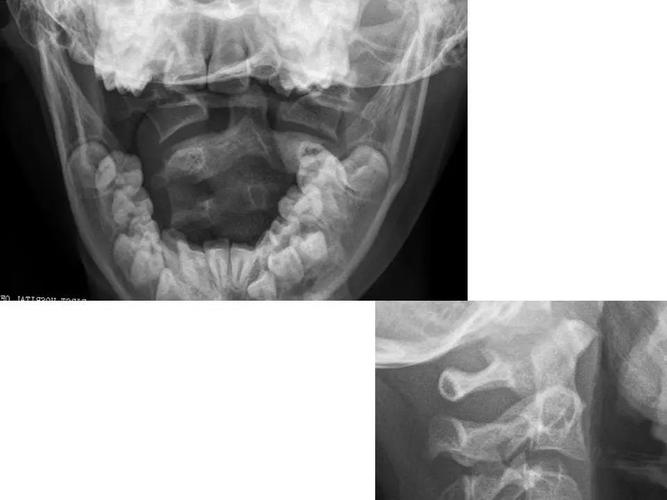

寰枢关节脱位的影像诊断